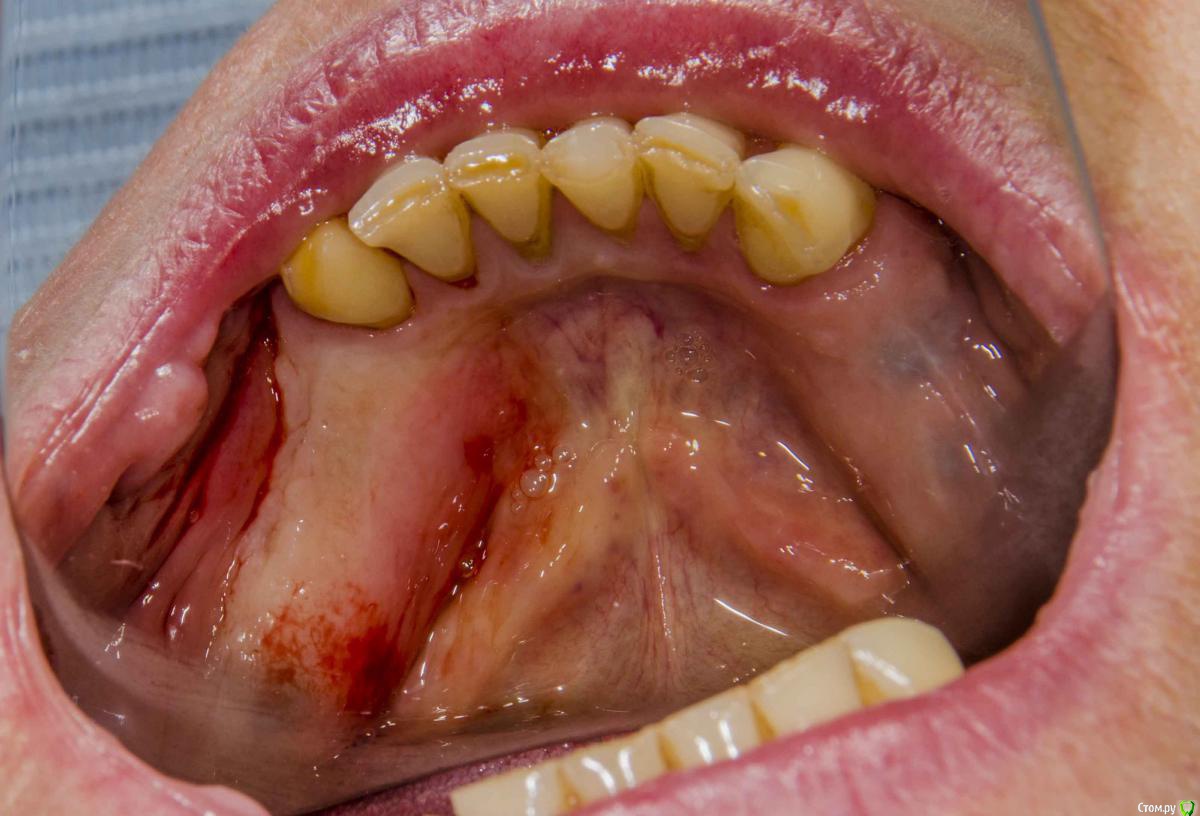

kamranchick Опубликовано 20 декабря, 2015 Поделиться Опубликовано 20 декабря, 2015 (изменено) Добрый день уважаемые форумчане, с наступающим друзья.хотелось бы спросить у Вас, частенько на этапе раскрытия сталкиваюсь с непонятными моментами, а именно, на НЧ иногда когда ушиваю рану получается вот так какая картинатам где не зашивали, картина выглядет более лучше чем там где зашивали)1 этап осмотр через 5 дней. и снятие швов2 этап осмотр через 2 неделиИзвините за качество фото, не умею фотографировать, вскоре этот недуг будет исправлен.Как Вы раскрываете имплантаты если они стоят рядом? точечно или как то по другому?ps работа была произведена давно, теперь там далеко от зубов не отступаю) Изменено 20 декабря, 2015 пользователем kamranchick Ссылка на комментарий

Доктор Хаус Опубликовано 20 декабря, 2015 Поделиться Опубликовано 20 декабря, 2015 По фото , где вы зашили лоскут, вы наложили шов так что нарушили питание вестибулярного лоскута . Лоскут ишемизировалься и начал умирать , шов должен только удерживать лоскут так чтобы он не шевелился. И не забывайте о кровяном сгустке . Ссылка на комментарий

Fake personage Опубликовано 20 декабря, 2015 Поделиться Опубликовано 20 декабря, 2015 (изменено) Соглашусь с предыдущим оратором."Задушил" лоскут.Ниточку потоньше ,точку вкола повыше)И по поводу фдм соглашусь тоже Изменено 20 декабря, 2015 пользователем Fake personage Ссылка на комментарий

Acidrocker Опубликовано 22 декабря, 2015 Поделиться Опубликовано 22 декабря, 2015 все дело в крестообразных швах, между точками вкола получилась хорошая зона ишемии. Ссылка на комментарий